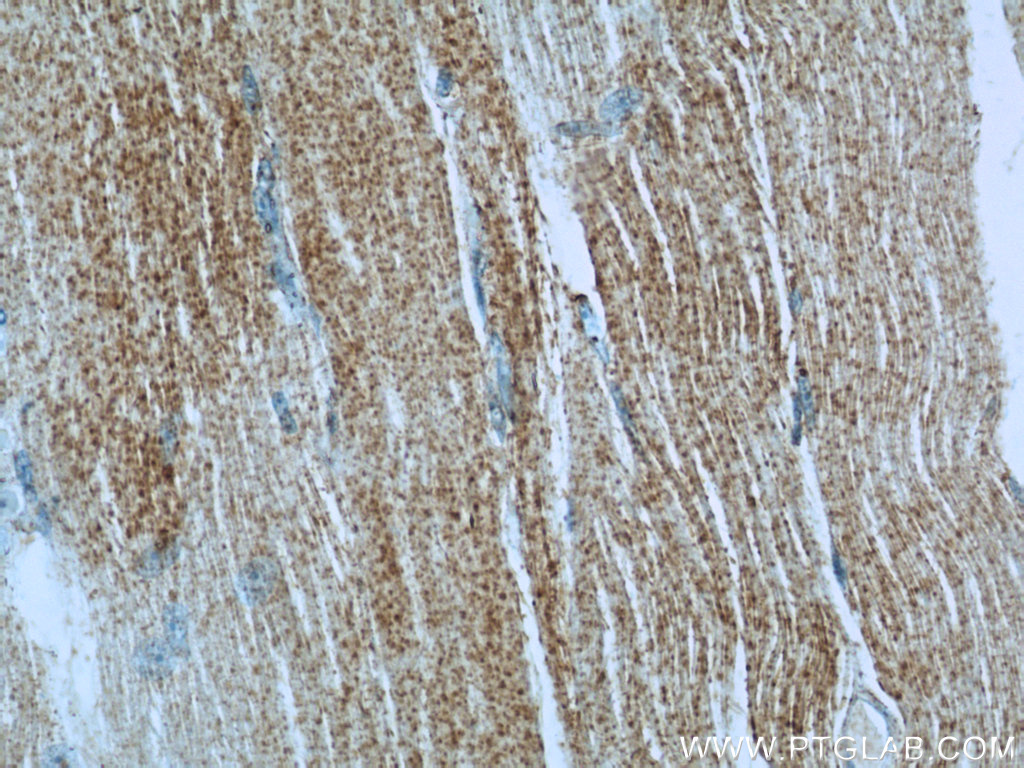

Supportive validation

- Submitted by

- Proteintech Group (provider)

- Main image

- Experimental details

- The IRGQ antibody from Proteintech is a rabbit polyclonal antibody to a fusion protein of human IRGQ. This antibody recognizes human antigen. The IRGQ antibody has been validated for the following applications: ELISA, WB, IHC analysis.